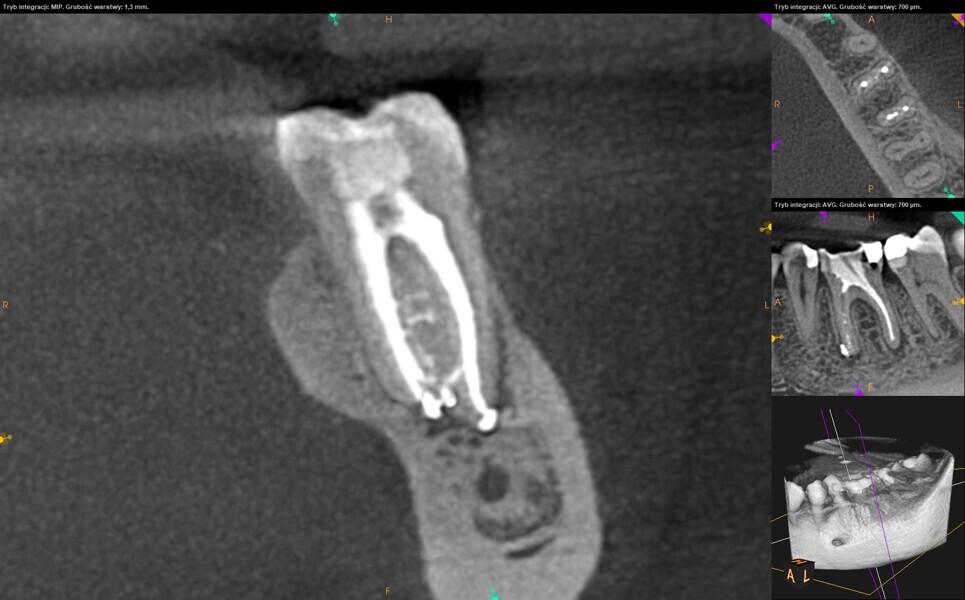

At the second appointment, the temporary restorations were removed, and the chlorhexidine was washed out with sterile water and EDTA. After opening the orifice of the MB2 canal in the first molar, the operator was not able to reach patency in the canal. Therefore, the isthmus between the MB1 and MB2 orifices was opened with diamond-coated ultrasonic tips. Finally, patency was reached. Shaping the MB2 canal in the second molar was possible only to the place of the junction with the MB1 canal. The CBCT imaging had revealed previously that the MB2 canal should have its own lumen in the apical third, but the place of the junction was below the curvature. The possibility of locating this space without damaging the root was very poor. At this stage, the LPE enhanced irrigation protocol was performed again. After performing of the irrigation protocol, the apical preparation was performed for all the canals. The final irrigation protocol was performed with 5 minutes of constant flow of 5.25% NaClO for 2 minutes, alternating with 17% EDTA for 30 seconds, with 5.25% NaClO for 30 seconds and 17% EDTA for 30 seconds, and irrigation with 5.25% NaClO for 5 minutes. All the irrigants were activated with an EDDY sonic tip (VDW). After performing the periapical radiographs, a CBCT scan was performed to confirm the separate path of the sealer that filled previously unprepared spaces of the MB2 canals in both teeth. In both cases, it was clearly visible on the CBCT image that all the previously unprepared spaces were filled with the obturation material.

A 25-year-old female patient presented to the office owing to constant pain related to the mandibular left first molar. Pulp necrosis was diagnosed. After the emergency appointment, the patient was referred for complete treatment. The tooth was treated in the same manner as described in the previous paragraphs. After creation of the access cavity, the orifices were located. In the root chamber, the orifices of the MB, mesiolingual, DB, distomesial and distolingual canals were present. After pre-flaring and preparation of the middle third, the LPE enhanced irrigation protocol with the SkyPulse laser was performed. After the irrigation protocol in the mesial root, the irrigants started to flow between lingual and buccal canals. Such an observation suggested to the operator that some space in the isthmus had been created. It is worth mentioning that at this stage apical enlargement was not performed. Final preparation of all five canals was performed with the reciprocating file, and the final irrigation protocol was performed as in the previous case. The radiograph clearly revealed that the isthmus space was filled with the sealer. The radiograph and CBCT image revealed that there were four portals of exit in the mesial root.

A 35-year-old female patient was referred to the office owing to the lack of patency in the pulp chamber. The periapical radiograph and CBCT image confirmed that the pulp chamber was completely calcified. The calcification of the pulp chamber was removed with diamond-coated ultrasonic tips. After removing the calcification, four orifices were located and shaped in the sequence described previously. The LPE enhanced irrigation protocol with the SkyPulse laser was performed. In this case, the MB2 canal joined the MB1 canal approximately 4 mm before the apex and was shaped only to this length. Apical preparation and irrigation were performed as described previously. The periapical radiograph revealed that the MB2 canal had a separate apical part, which was cleaned with the irrigants and filled with the sealer, and that the palatal canal had two portals of exit.

The in vitro trials and in vivo cases, periapical radiographs and postoperative CBCT images demonstrate that the laser activation of irrigants allows the clinician to achieve much better removal of the hard-tissue debris than with the conventional irrigation methods. The LPE concept appears promising in terms of the improved removal of hard-tissue debris. It is important to mention that this is only a clinical observation. The most important part of this observation is a very rapid flow of the irrigants between the root canals located in the same root after the LPE enhanced irrigation protocol with the SkyPulse laser but before apical preparation.